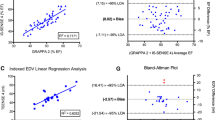

The scores of individual patients, clustered by sequence type, are illustrated in a scatter plot in Fig. 5. The PSIR group showed the least variation in scores. Furthermore a high number of maximum scores (30 points) was noted in the PSIR group (26%) compared to 19% in the 2D group. No maximum scores were reached in the 3D group.

The clinical suitability score was divided in three categories as shown in Fig. 6. Clinically suitable scans (with a score of 25 or higher) were seen in 90% of all exams in the PSIR group, 75% of the 2D group, and in only 7% of the 3D group.

Breathing artifacts were more frequent in the 2D (59%) and PSIR (53%) sequence compared to the 3D sequence (22%). Motion artifacts occurred most frequently in the 3D group (55%) as compared to the PSIR 29% and 2D 28% group. Nulling of the normal myocardium was considered to be correct in 96% of the 3D scans, 95% of the PSIR scans and 91% of the 2D scans.